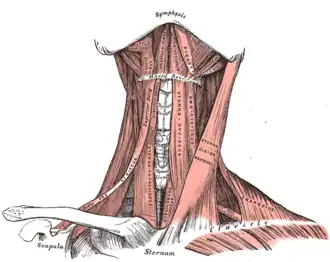

Muscles of the neck. Anterior view. | |